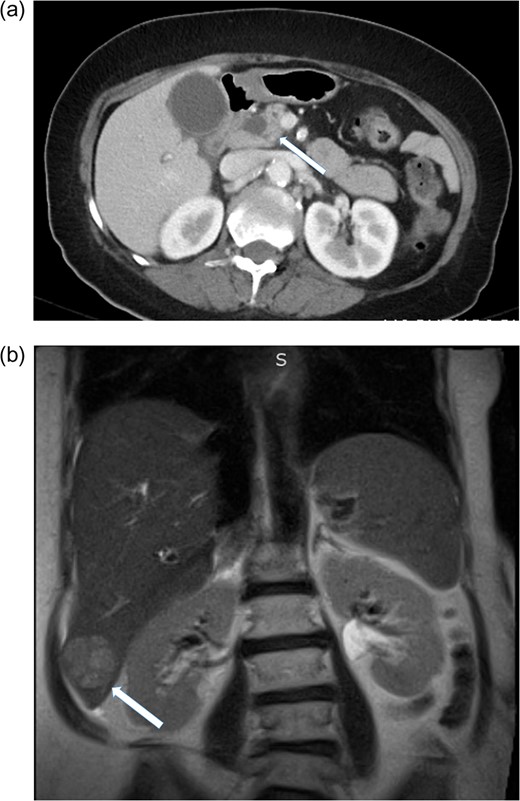

A 70-year-old woman presented with right-sided abdominal pain, nausea, vomiting and fever. She had a history of diabetes, hypertension and hypercholesterolemia. She smoked 0.5 pack/day and denied alcohol abuse. There was no significant family history. On admission her vital signs were within normal limits. On physical exam her sclera were anicteric. Her abdomen was soft, non-tender, non-distended with no palpable masses. Labarotory studies revealed: Alk Phos 126 IU/L, total bilirubin 2.0 mg/dL, AST 63 IU/L, ALT 58 IU/L, tumor markers showed AFP 226 ng/mL (normal 0.0–8), CA 19-9 959 unit/mL (normal 0–35) and carcinoembryonic antigen (CEA) 3.9 ng/mL (normal 0–3). Hepatitis C antibody was reactive and Hepatitis B core AB negative. CAT-scan of the abdomen revealed a 1.3 cm mass in the head of the pancreas with intrahepatic and extrahepatic ductal dilatation (Fig. 1a). MRI of the abdomen showed a 3.7 cm mass in segment VI of the liver (Fig. 1b). ERCP with bile duct brushings was performed and consistent with malignancy. EUS demonstrated a 2.6 cm mass in the head of the pancreas with portal vein involvement. Ultrasound guided biopsy of the liver was consistent with HCC. (Fig. 2). Routine staging CT scan of the chest showed a prominent 2.1 cm pre-tracheal lymph node. Endobronchial ultrasound guided-fine needle aspiration (FNA) of this lymph node showed no evidence of malignant cells.

(a) CT scan of the abdomen showing pancreatic mass, solid arrow. (b) MRI of the abdomen showing segment six hepatic lesion, solid arrow.

Care should be taken to rule out metastatic disease in patients with synchronous malignancies particularly when one of the lesions is hepatic. In this case the possibility of synchronous intra and extrahepatic biliary tumors was not considered given the radiographic characteristics of the hepatic lesion. The MRI revealed a hyperintense lesion, heterogeneous enhancement with central washout and delayed capsular enhancement, consistent with primary hepatocellular carcinoma.